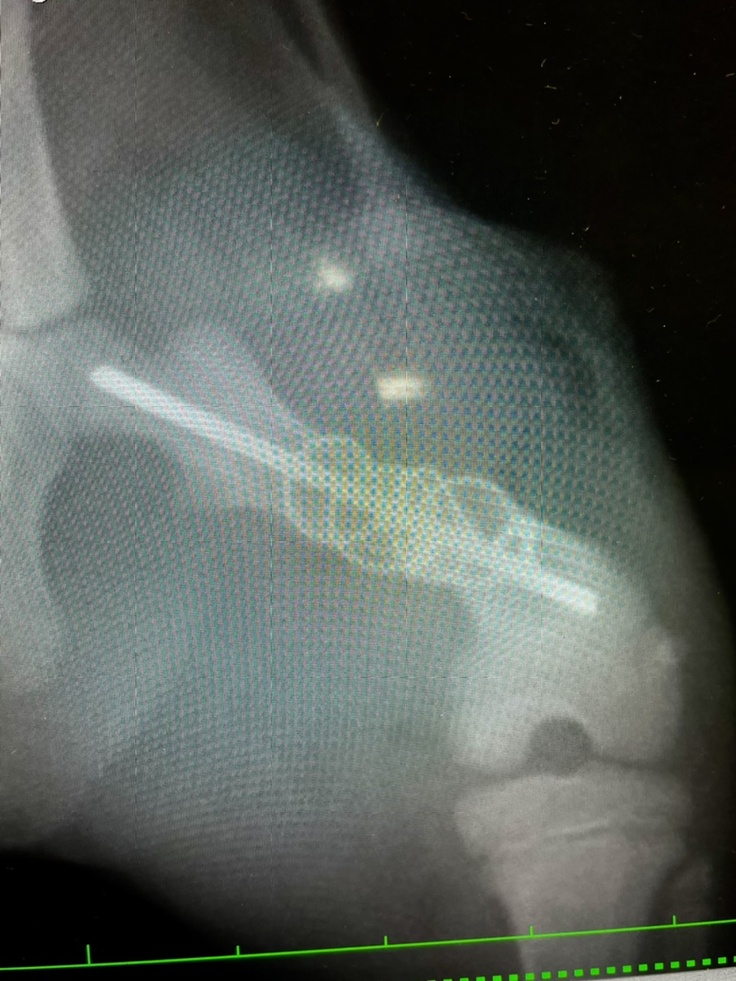

レントゲンの結果、左後脚大腿骨が3つに分かれていました。普通の骨折ではなく、粉砕骨折を患い、また腰骨も負傷している可能性があり、4本の足で立つことすら難しい状態でした。左後脚は力が入らず、ぶら下がってました。左後脚は手術が必要とのことで、すぐ手術の段取りをしました。

8月20日に無事に手術が終わり、8月21日に退院しました。ステンレスのピンとワイヤーで骨を固定しています。服薬は難しいとのことで2週間効果が続く抗生剤の注射を退院時に接種しています。

今後1週間に1度通院し、診察やレントゲン撮影で経過観察を継続し、必要に応じて抗生剤などの投薬治療やリハビリを行う予定です。

またもしピンが術後2週間以内に体外に出てきてしまった場合、骨の融合が不十分な為、もう1度同じ手術をする可能性があるとのことでした。

縫合後の皮膚の治りは順調です。骨も少しずつですが、くっついてきています。しかし固定したピンがズレてきているため、皮膚を突き抜け、飛び出してくる可能性があるとのことでした。飛び出してきた場合はまた抜き取る処置をしなくてはならないとのことでした。次の受診は9/11を予定しています。

レントゲン撮影を行いました。

骨は綺麗に治ってきています‼︎

しかしピンの位置がズレてきていて、このままでは皮膚を突き破るので、そうなる前にピンを取り除くため、再手術を行うことになりました。本来であればピンを温存する予定でしたが、今の骨の状態であればピンを取り除いても大丈夫とのことでした。

次の受診日の9月16日に再手術を行う予定です。

8月20日に手術をした時には膝関節から大腿骨にかけてピンを入れてましたが、今はピンの位置がズレいて、お尻の皮膚が盛り上がり、突き破りそうになっています。

8月31日と9月11日に撮ったレントゲンを比べても、かなりピンの位置が違います。

↓[8月31日撮影]

↓[9月11日撮影]

ピンが皮膚を突き破りそうなため、摘出を行いました。幸い抜き取る事が出来たので、切開も小さい範囲で済みました。ワイヤーは残したままです。

レントゲンを撮り怪我の経過を見て頂きました。最初は骨が散らばっていたので、まだ骨と骨との間に隙間はありますが経過は良好とのことでした!ワイヤーは入れたままで、今後も生活を送ります。